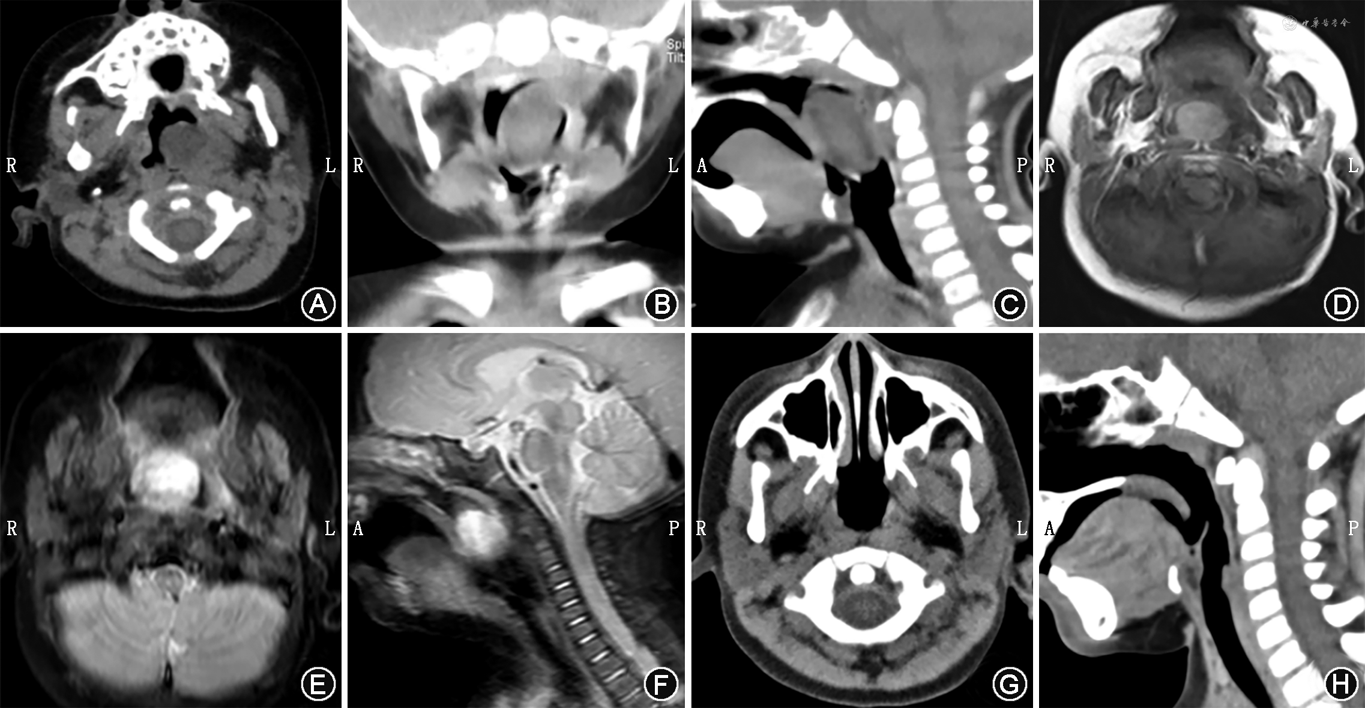

患儿,男,6个月,因“呼吸困难2个月,加重2 d”于2019年4月7日入院。2个月前患儿无明显诱因出现呼吸困难,喝奶时常需换气,无咳嗽、发热,无意识障碍,就诊于当地社区医院建议观察随诊;2 d前患儿呼吸困难加重,活动时更明显,遂就诊于当地妇幼保健院,胸部X线片提示支气管肺炎,建议就诊上级医院,遂至我院就诊。患儿既往体健,否认“支气管哮喘”等系统疾病史。查体:神志清醒,精神状态尚可,发育正常,营养良好,急性面容,呼吸困难。专科查体:口咽部见一光滑灰白色新生物,咽腔狭窄;哭闹时吸气相见锁骨上窝、胸骨上窝明显内陷。外院血液检查提示:白细胞11.78×109/L;入院后血常规提示:白细胞22.77×109/L。影像学检查(CT和MRI)提示左侧鼻咽部肿物(图1)。

入院后经检查初步诊断为:(1)鼻咽部囊肿?;(2)左中耳乳突炎;(3)肺部感染。为进一步治疗及明确诊断,2019年4月11日于全身麻醉下经鼻内镜行鼻咽部新生物切除术。开口器暴露口咽部,导尿管经鼻腔拉起软腭,70°鼻内镜下见左侧咽鼓管咽口及鼻咽部灰白色、灰褐色光滑息肉样实性组织,质地中等,根蒂位于左侧咽鼓管内;完整剥离肿物后探查左侧、右侧咽鼓管,见左侧咽鼓管咽口较右侧扩大,未见新生物残留,标本送病理。术后给予抗感染治疗,患儿呼吸通畅,5 d后出院。病理回报:左侧咽鼓管新生物表面衬覆假复层纤毛柱状上皮,黏膜下层为疏松结缔组织,散在淋巴细胞浸润,其内见成熟脂肪组织,病理诊断为复合性迷离瘤;鼻咽部新生物表面衬覆未角化成熟鳞状上皮,黏膜下层见皮脂腺及增生并玻璃样变性的纤维结缔组织,病理诊断为单纯性迷离瘤(图2)。术后1个月、6个月、1年、2年间断随访,患儿无呼吸困难及吞咽困难。术后2年随诊,耳内镜下见双耳鼓膜完整、标志清;声导抗检查左耳鼓室图A型曲线,右耳As型曲线;鼻内镜下见左右鼻咽部对称,左侧咽鼓管咽口光滑,未见新生物(图3);复查鼻咽部CT,未见复发迹象。